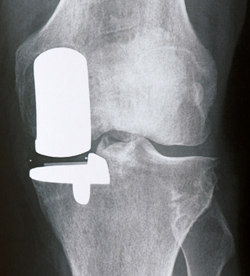

X-ray of Biomet Oxford Partial Knee Replacement

Biomet Oxford Partial Knee Replacement

The pictures show a Biomet Oxford Partial Knee Replacement and a Vanguard Total Knee Replacement. The patella is not shown on these images.